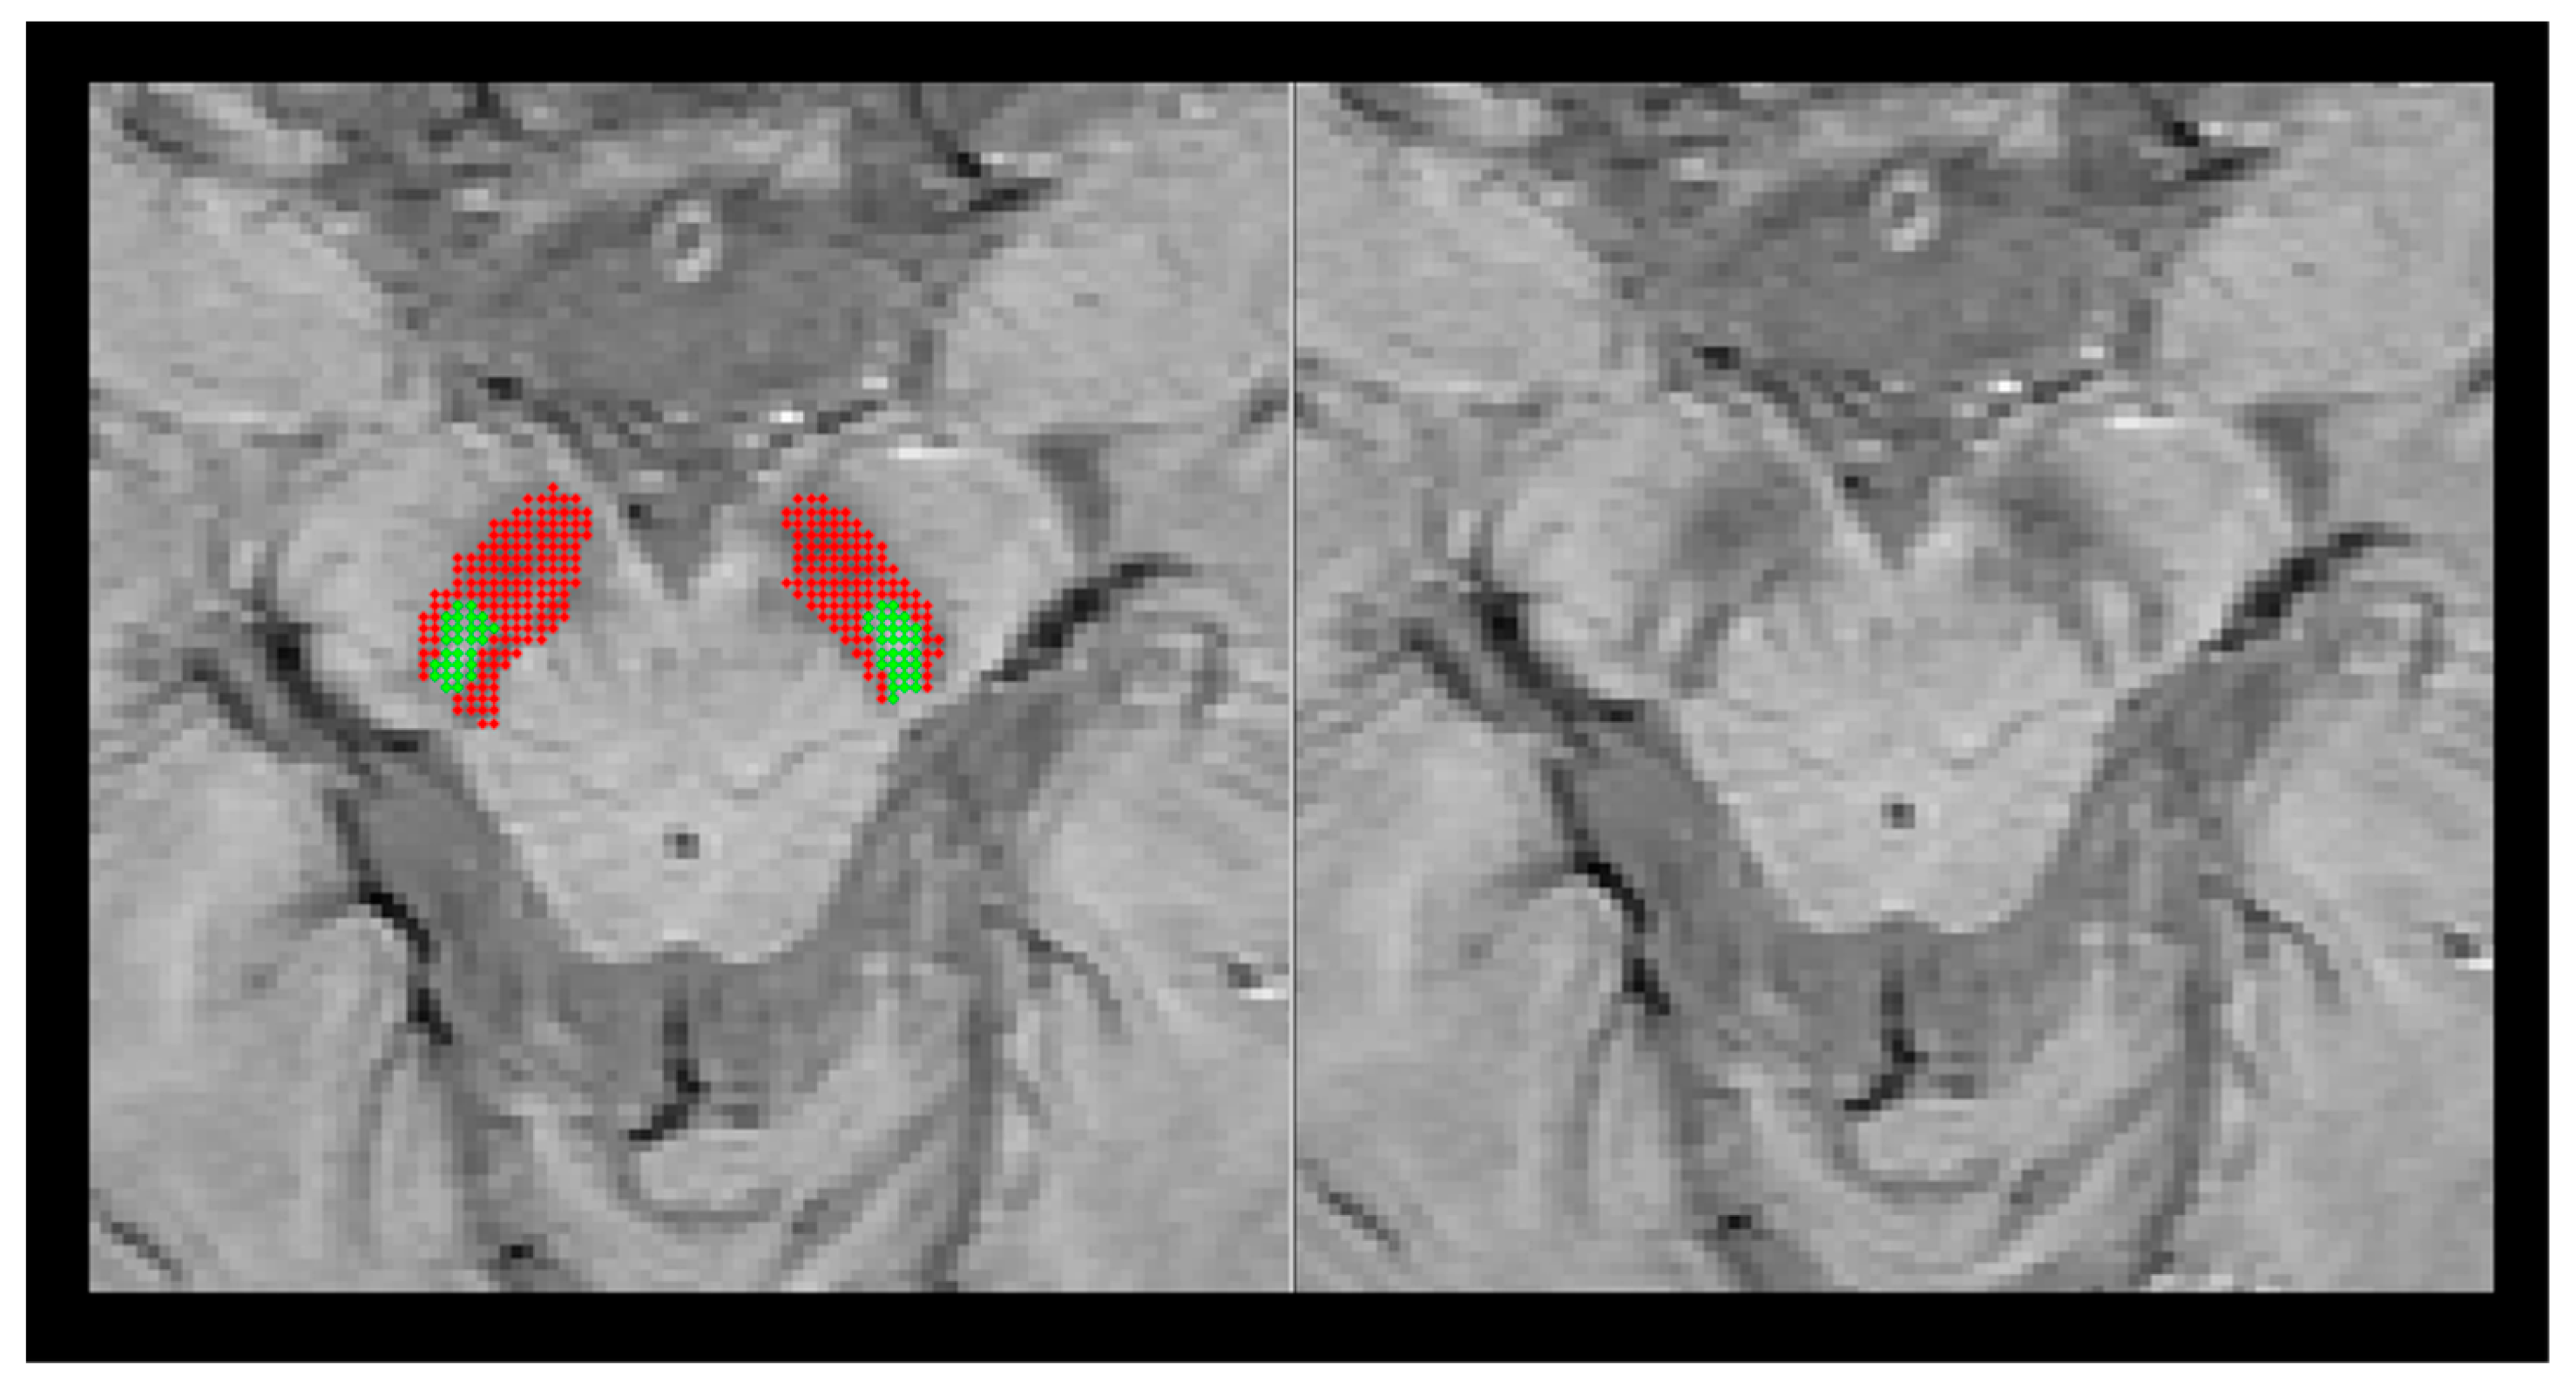

| QSM | T2* | Phaave | ||||||

|---|---|---|---|---|---|---|---|---|

| SN1 | S0 | SN1 | S0 | SN1 | S0 | |||

| 64CH | Older | Mean (std) | 90.20 (33.01) | 136.99 (43.38) | 36.02 (5.86) | 25.26 (5.04) | −0.02 (0.01) | 0.02 (0.02) |

| Young | Mean (std) | 53.16 (29.19) | 85.52 (37.27) | 38.86 (4.49) | 28.94 (4.85) | −0.02 (0.01) | 0.03 (0.02) | |

| p-value a | <0.001 * | <0.001 * | 0.55 | 0.13 | 0.29 | 0.57 | ||